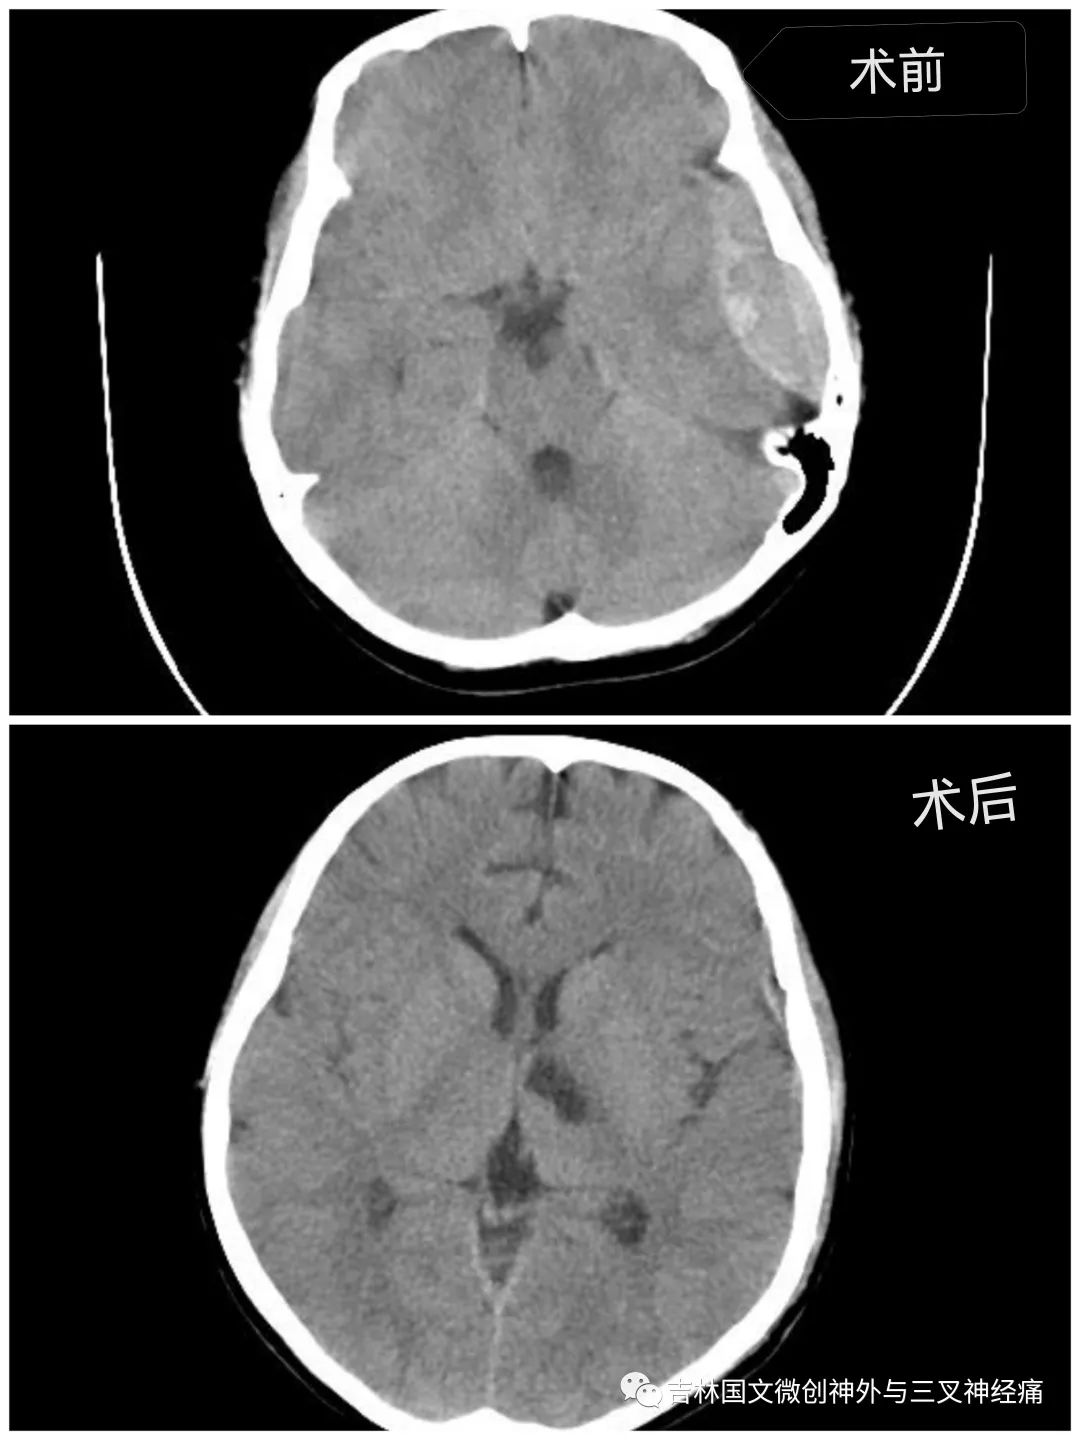

急促的車(chē)輪聲刺激著所有人的神經(jīng)?!昂⒆踊杳?,顱內(nèi)出血量大,左側(cè)瞳孔散大,已腦疝,需要緊急診開(kāi)顱手術(shù)”?!跗M主任向家屬交代著。家屬滿臉的焦急,并未有過(guò)多的猶豫,立即決定手術(shù)。從病人同意手術(shù)到進(jìn)入手術(shù)室,前后近用了20幾分鐘。

在王芃主任的帶領(lǐng)下,手術(shù)室的鼎力支持下,歷時(shí)近4個(gè)小時(shí),手術(shù)順利完成。由于病人腦損傷很重,一直處于昏迷狀態(tài)。為了能讓孩子的未來(lái)不至于太自卑,少受一點(diǎn)損傷,少留下一道疤痕,王芃主任帶領(lǐng)他的團(tuán)隊(duì)用盡一切辦法在努力的保護(hù)病人的氣管(嚴(yán)重腦損傷、長(zhǎng)期昏迷的病人,為了能保證呼吸道通暢,增加病人的活命幾率,一般都需要進(jìn)行氣管切開(kāi))。